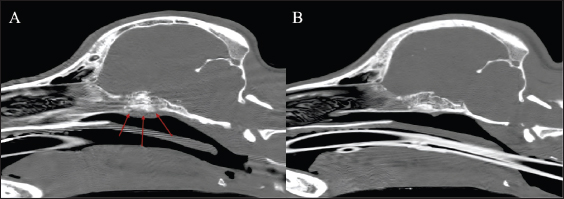

The dog received general anesthesia and underwent a computed tomography scan of the head and cervical vertebral column before and after iodinated intravenous contrast injection with iohexol at 400 mg/kg (Omnipaque, General Electrics Healthcare, Cork, Ireland). Anesthesia was induced with propofol (Propomitor, Orion Pharma, Madrid, Spain) at 4 mg/kg IV and was maintained with 1.5% isoflurane (Isofane, Piramal Critical Care B.V., Voorschoten, Netherlands) in oxygen under controlled ventilation. A 16-slice helical CT scanner (Brivo CT385, General Electrics Healthcare, Madrid, Spain) was used for imaging acquisition. The images revealed an aggressive polyostotic, osteolytic, and osteoproliferative lesion with periosteal reaction affecting the basisphenoid and presphenoid bones and, therefore, compromising the optic canal and orbital fissure (Fig. 1). The lesion extended intracranially at the level of the rostral and middle cranial fossa as an isoattenuating, ill-defined extra-axial space-occupying mass with marked and homogenous contrast enhancement (Fig. 2). No abnormalities were found in the cervical column images. A cisternal cerebrospinal fluid tap was performed, and the sample was analysed, the results of which were within the reference ranges. Polymerase chain reaction in the cerebrospinal fluid was not performed as the total nucleated cell count was within normal limits.

Fig. 1. Bone window (A) pre-treatment sagittal reconstruction and (B) post-treatment sagittal reconstruction of the head, revealing the osteolytic and osteoproliferative lesions (arrows) affecting the sphenoid bone and its resolution after treatment.

The dog was treated with a 4-week course of 100 mg/kg meglumine antimoniate (Antishmania, Fatro ibérica, Barcelona, Spain) subcutaneously once daily and 10 mg/kg alopurinol (Alopurinol Normon, Normon, Madrid, Spain) orally twice daily. In addition, prednisone (Prednisona Cinfa, Cinfa, Huarte, Spain) at 0.5 mg/kg twice daily orally was administered for 7 days to treat the possible vasogenic edema secondary to the inflammatory response produced by the intracranial lesion. No side effects were witnessed by the owner, and the dog tolerated the treatment well. Two and a half months after diagnosis, the dog was presented for a recheck. The physical and neurological examinations did not reveal any abnormalities. Additionally, the dog was reported to be clinically normal. A follow-up head CT scan with intravenous contrast was performed to evaluate the progression of the sphenoid bone lesions (Fig. 1). The previously described osteolytic and osteoproliferative lesions had healed, and the extra-axial mass lesion had resolved. Simultaneously, a follow-up proteinogram showed an improvement in the monoclonal gammopathy. During a telephone consultation 5 months after diagnosis, the owner reported that the dog was clinically normal and had an excellent quality of life. At that time, the dog was still receiving alopurinol, and the treatment was monitored by the referring veterinarian. Additional serological evaluations were declined due to financial constraints.